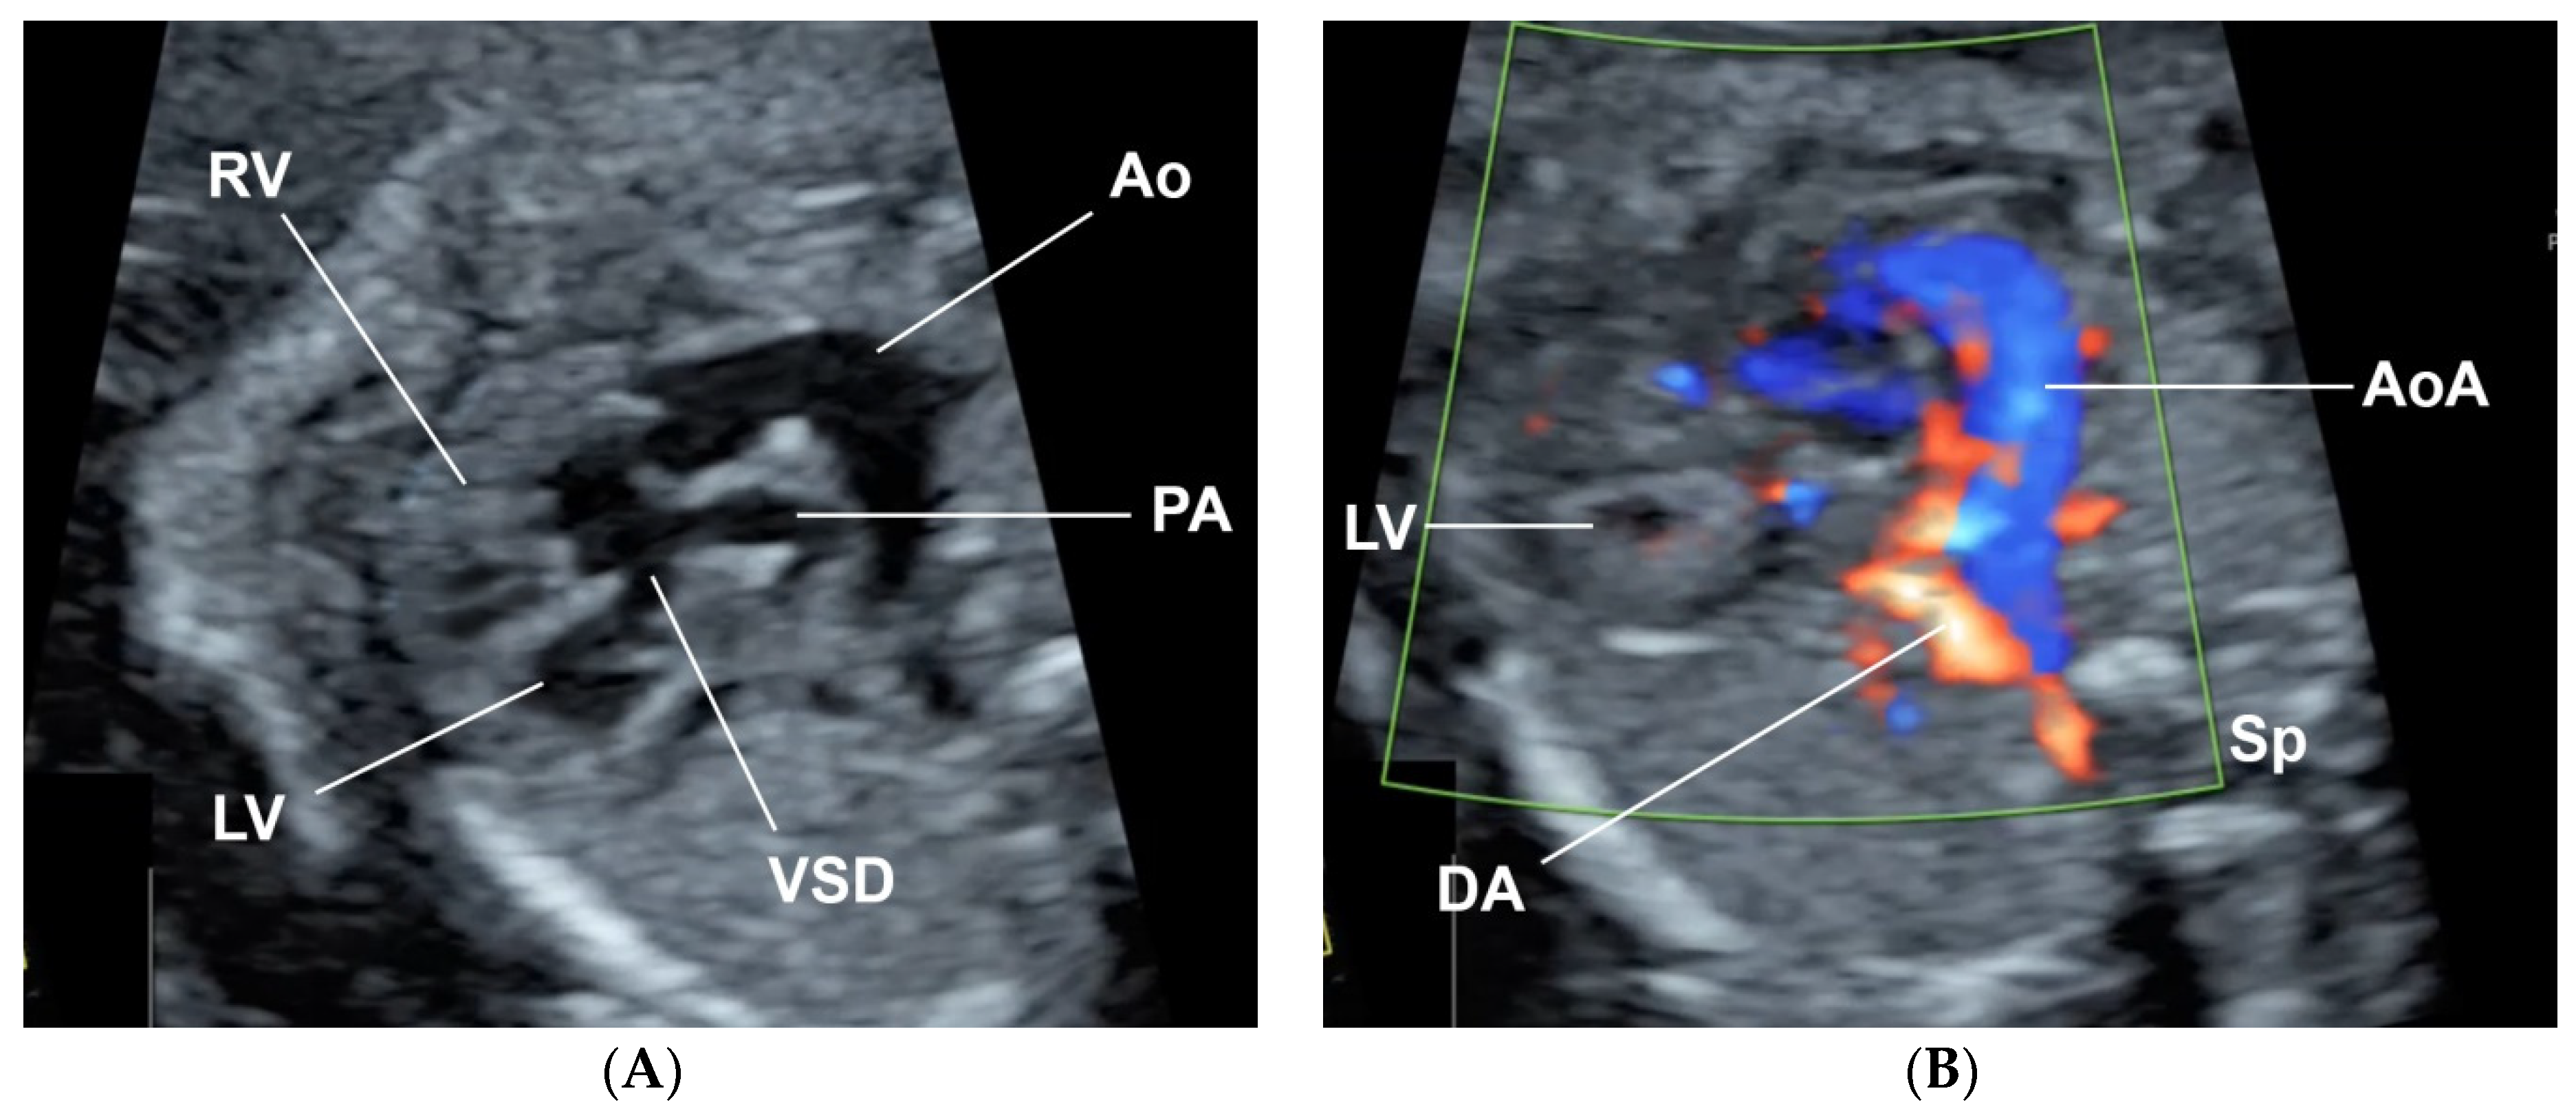

A 32-year-old pregnant woman, G4 P2102, attended her first visit of antenatal care at 23+3 weeks of gestation. Ultrasound examination for anomaly screening demonstrated cardiac defects, including double-outlet right ventricle: DORV-TOF type, with severe pulmonary stenosis (Figure 1) and left superior vena cava. Detailed ultrasound showed no associated abnormalities. Fetal biometry was consistent with gestational age except abdominal circumference and estimated fetal weight, which were relatively low (at 10th percentile), reflecting some degree of growth restriction. However, detailed ultrasound on the follow-up scans at 28 weeks of gestation showed subtle abnormalities, including malrotation of both kidneys, the hilum or renal pelvis facing posteriorly to the abdominal wall (Figure 2). Furthermore, 3D-ultrasound revealed abnormal external ear structure (markedly prominent crus of anti-helix) (Figure 3). Non-stress tests (NST) showed spontaneous fetal heart rate (FHR) accelerations (normal reactive tests) (23+3 weeks). Interestingly, the fetus showed persistent non-response to acoustic stimulation tests at 26, 30, 32, 36 and 38 weeks (no FHR accelerations as well as no quickening perceived by ultrasound) (Figure 4), probably reflective of auditory dysfunction. Based on the findings of heart defect, ear defect, renal defect and growth restriction, several differential diagnoses were listed, including CHARGE syndrome. Theoretically, fetal blood sampling for molecular genetic tests should be performed. Nevertheless, since no lethal condition was identified and the couple wanted to continue pregnancy regardless of investigation results, prenatal invasive diagnosis was avoided, and we waited for postnatal work-up instead. She had no significant underlying disease and no familial history of hereditary diseases. Her pregnancy was uneventful except that she developed gestational diabetes (GDM) at 28 weeks of gestation, which was well-controlled with diabetic diet.

Figure 1. Double-outlet right ventricle (DORV): (A) TOF type, small pulmonary artery (PA) and (B) reverse flow in the ductus arteriosis (DA) (Ao: ascending aorta; AoA: aortic arch; LV: left ventricle; RV: right ventricle; Sp: spine; VSD: ventricular septal defect).

Figure 3. 3D-Ultrasound: Abnormal ear; markedly prominent superior crus of anti-helix.